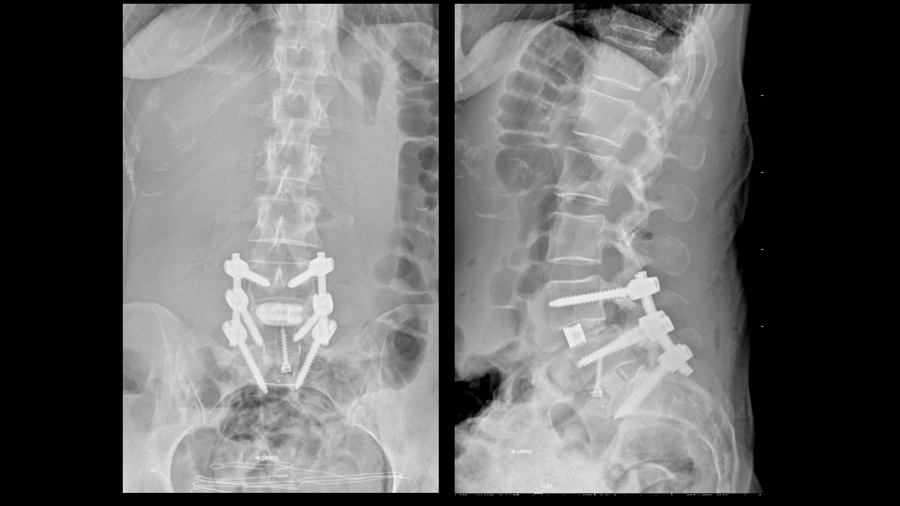

L5–S1 was treated with anterior lumbar interbody fusion (ALIF) to facilitate lordosis restoration. A 12-degree cage was used, with the acknowledgment that greater lordosis might have been achievable with a higher-angle implant. L4–5 was treated with posterior decompression and TLIF. Emphasis was placed on using a large, anteriorly positioned cage, posterior column osteotomy and compressing through the posterior column to maximize segmental lordosis.

Postoperative imaging demonstrated restoration of alignment and stable fixation from L4 to S1. However, what was particularly striking was the effect on the non-fused segments:

High pelvic incidence is typically associated with a steep sacral slope, which generates significant shear forces at the L5–S1 junction. This mechanical environment increases the risk of loosening and pseudarthrosis. In this patient, strategies to counteract these forces included bicortical S1 screws and a large-footprint interbody implant.

At 15-month follow-up, CT imaging confirmed a solid fusion. For the treating surgeon, this confirmation provided confidence in the durability of the result. In high PI patients, achieving reliable fusion is not an accessory goal; it is fundamental to the overall success of the operation.